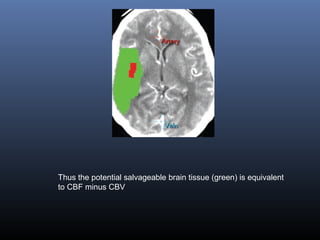

(b–e) Perfusion CT maps of MTT (b), CBF (c), and CBV (d) and a summary

map (e) show altered MTT and CBF in the right frontotemporal area, suggestive of

ischemia, and a small subcortical area with decreased CBV, suggestive of an

infarcted core. Note the area of increased CBF and CBV in the right caudate and

lenticular nucleus, representing the first stage of brain ischemia (compensatory

supply with cerebrovascular reserve). Thus the potential salvageable brain tissue is

equivalent to CBF minus CBV

Thus the potential salvageable brain tissue (green) is equivalent

to CBF minus CBV